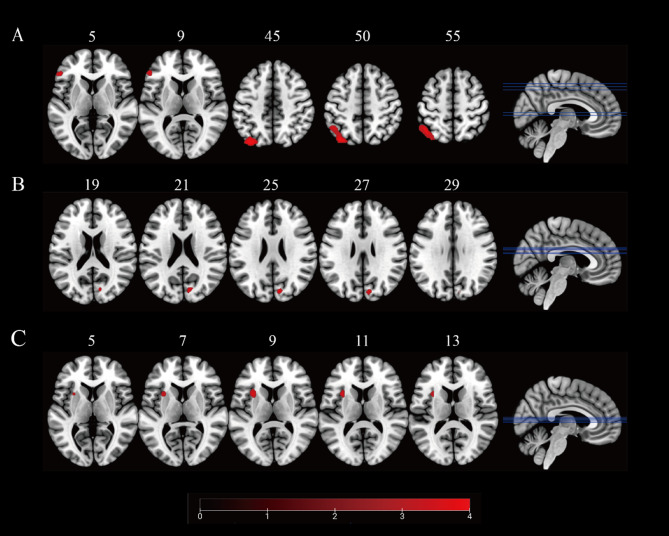

背景:躯体症状在青少年重度抑郁障碍(MDD)中很常见,并与抑郁的严重程度和临床结果相关。然而,青少年MDD的躯体症状的神经机制仍不清楚。在这项研究中,我们旨在探讨基于静态和动态区域均匀性(ReHo)的青少年MDD伴躯体症状的内在脑局部连通性的功能改变。方法:本研究纳入50例首发、药物naïve青少年MDD患者和34例年龄、性别和受教育年限相匹配的健康对照(hc)。根据有无躯体症状将患者分为躯体抑郁(SD)组(n = 21)和非躯体抑郁(NSD)组(n = 29)。所有参与者进行静息状态功能磁共振成像(rs-fMRI),计算SD组、NSD组和HC组的静态和动态ReHo并进行比较。通过相关分析评估ReHo值改变与临床症状严重程度之间的关系。结果:有躯体症状的青少年MDD患者在17项汉密尔顿抑郁量表(HAMD-17)总分中得分较高。SD组左侧顶叶下回(IPG)、左侧顶叶上回(SPG)和左侧额叶下回三角区(IFGtriang)静态ReHo均较NSD组升高。SD组也表现出双侧IPG、双侧SPG和左iftriang动态ReHo降低。此外,这些异常脑区的静态和动态ReHo值与HAMD-17权重因子评分之间存在显著相关性。结论:本研究提示青少年MDD躯体症状患者SPG、IPG和IFGtriang可能存在异常的局部功能连接模式,丰富了青少年MDD躯体症状的神经学机制。

Results: Adolescent MDD patients with somatic symptoms showed higher total scores of the 17-items Hamilton Depression Scale (HAMD-17). Moreover, increased static ReHo in left inferior parietal gyrus (IPG), left superior parietal gyrus (SPG) and left triangular part of inferior frontal gyrus (IFGtriang) were observed in SD group compared with NSD group. The SD group also exhibited decreased dynamic ReHo in bilateral IPG, bilateral SPG, and left IFGtriang. Moreover, there were significant correlations between static and dynamic ReHo values in these abnormal brain regions and the weight factor scores of HAMD-17.